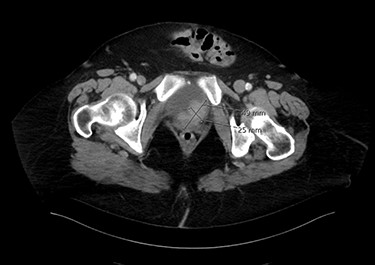

Seventy-year-old gentleman presented with an attack of gross hematuria and computed tomography scan showing irregularly thickened bladder wall. Endoscopic resection confirmed T1 MPBC. Induction course of BCG was provided. Cystoscopy showed small mass recurrence and pathology was muscle-invasive MPBC. Radical cystoprostatectomy sparing the urethra was done. Pathology was T2 MPBC with negative surgical margins and negative for lymph nodes invasion. He developed bleeding per urethra 6 months later and urethrectomy was done showing micropapillary cancer involving the urethra. Figure 2 shows an axial image of the bladder tumour.